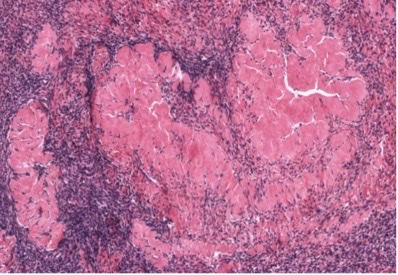

corpus luteum

atretic follicle, corpus luteum, or corpus albicans?

temporary endocrine structure that produces estrogens to regulate uterus

function of corpus luteum

granulosum and follicular theca left behind by ovulated mature oocyte

what is the corpus luteum made of?